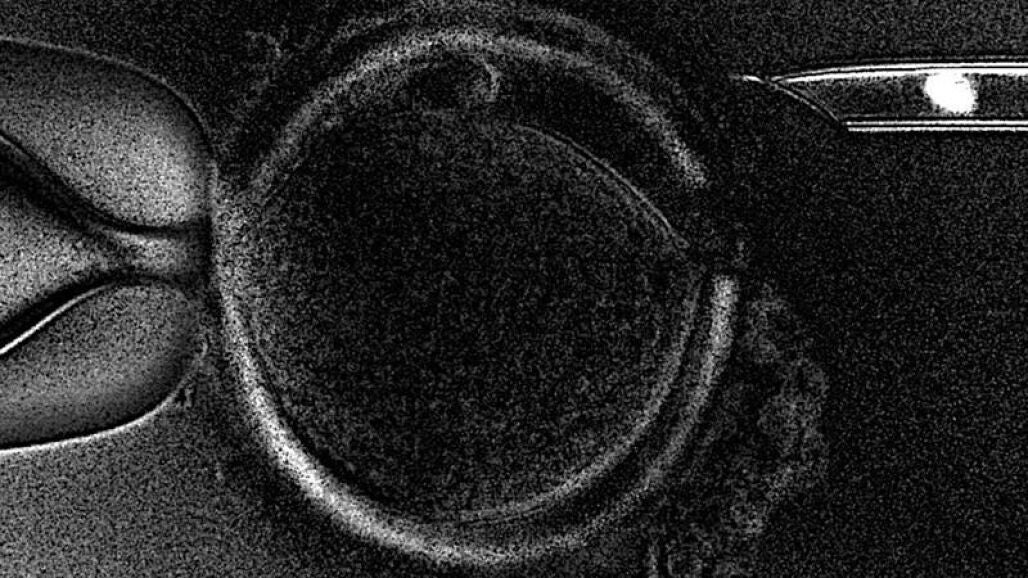

"Esta técnica puede abrir una nueva era en la reproducción asistida", declaró el director científico de Embryotools, que tiene su sede en Barcelona, Nuno Costa-Borges, desplazado a Atenas para atender el parto. La novedad de la técnica de la Transferencia de Huso Materno (MST, en sus siglas en inglés) es que permite que mujeres que no consiguen el embarazo con tratamientos in vitro convencionales -que usan el material ovárico de la paciente-, puedan hacerlo con la ayuda de una donante de óvulos pero sin renunciar al propio material genético. Esto es posible porque se extrae el huso meiótico (núcleo) de un ovocito (óvulo inmaduro) no fecundado de la paciente, dónde se encuentra el ADN, y se implanta en un ovocito sano proveniente de una donante, al cual a su vez se ha retirado previamente su núcleo.

De esta forma, el óvulo resultante contiene el material genético de la paciente pero el resto de componentes, que tienen un papel crucial en la salida adelante del embrión, son de una donante sana. Este óvulo es, finalmente, fecundado con el esperma de la pareja e implantado en la paciente. Costa-Borges explicó que el nacimiento del primer bebé es "la última prueba que quedaba" para demostrar que se trata de "una técnica segura y eficiente", investigada durante más de cinco años por el equipo de Embryotools, y que les valió un premio de la Sociedad Americana de Medicina Reproductiva (ASRM).